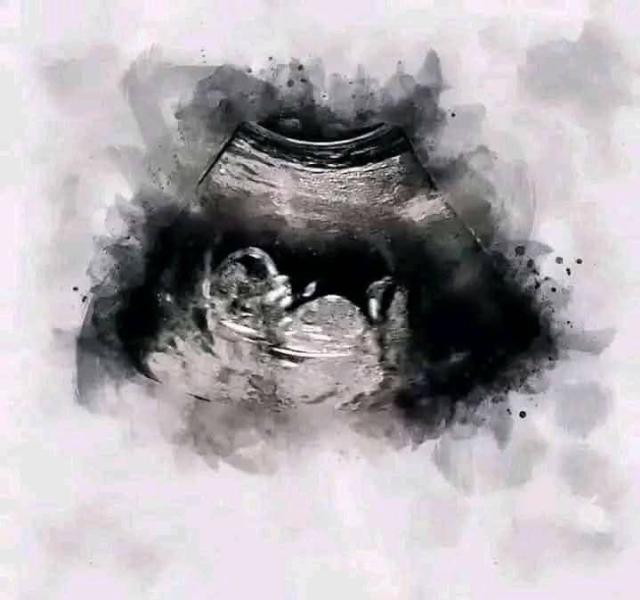

Сегодня 13 недель, 3 дня.

Скрининг пройден. И по УЗИ и по крови все риски низкие. 🙏🏻